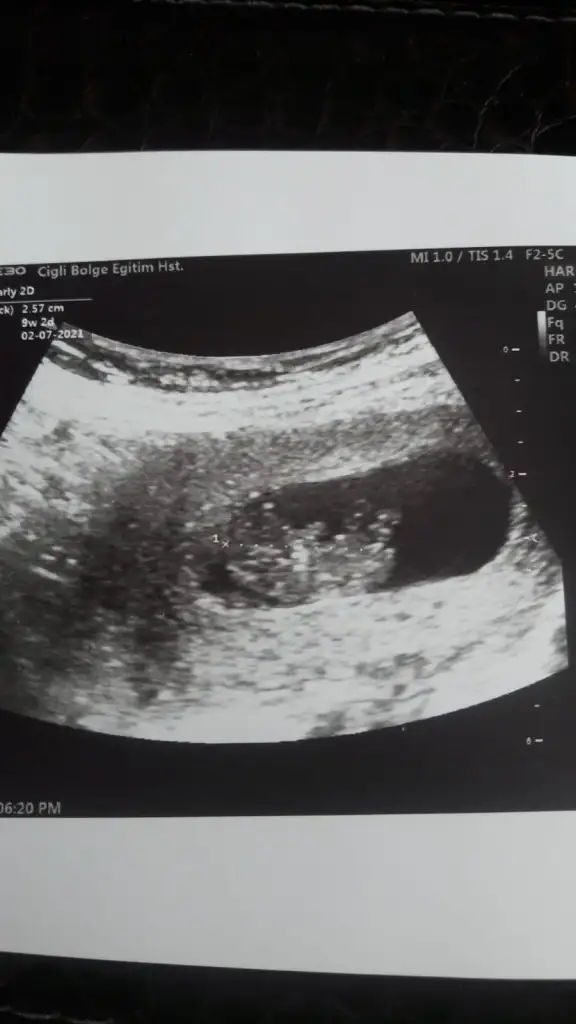

Tesekkur ederim yorumunuz icin dr %70 kız dedi.bende erkege benzetmistimNubu ne dik nede paralel emin olamadım ama sanki yapısı erkek gibi geldi bana

Önceki usg kaç haftalıktı kese arada tutmuyor cnm hayırlısı olsun sizin içinBu haftaya kadar erkek dedin canım nubda kız diyorsan kızdır ozaman nasip doktorda emin değilim ama kıza benziyor dedi 3. Kızımız gelecek bu durumda

Evet nub tam dik gelmedi ama şekli tipi erkek gibi geldi hayırlısı olsun cnmTesekkur ederim yorumunuz icin dr %70 kız dedi.bende erkege benzetmistim

Ayyy cnmmm hadi inşallah iki oğlum var kız için deli oluyorum en son o var bayramdan sonra cinsiyet ogrencem hadi inşallah çok teşekkür ederimTahmin etsem dogru olmaz tahminin yanlış dersiniz12-13 hafta olursa paylaşın şimdilik kız ama şimdilik emin olamadım

Ama emin değilim yazdım olursa 13 hafta paylaşınAyyy cnmmm hadi inşallah iki oğlum var kız için deli oluyorum en son o var bayramdan sonra cinsiyet ogrencem hadi inşallah çok teşekkür ederim ❤